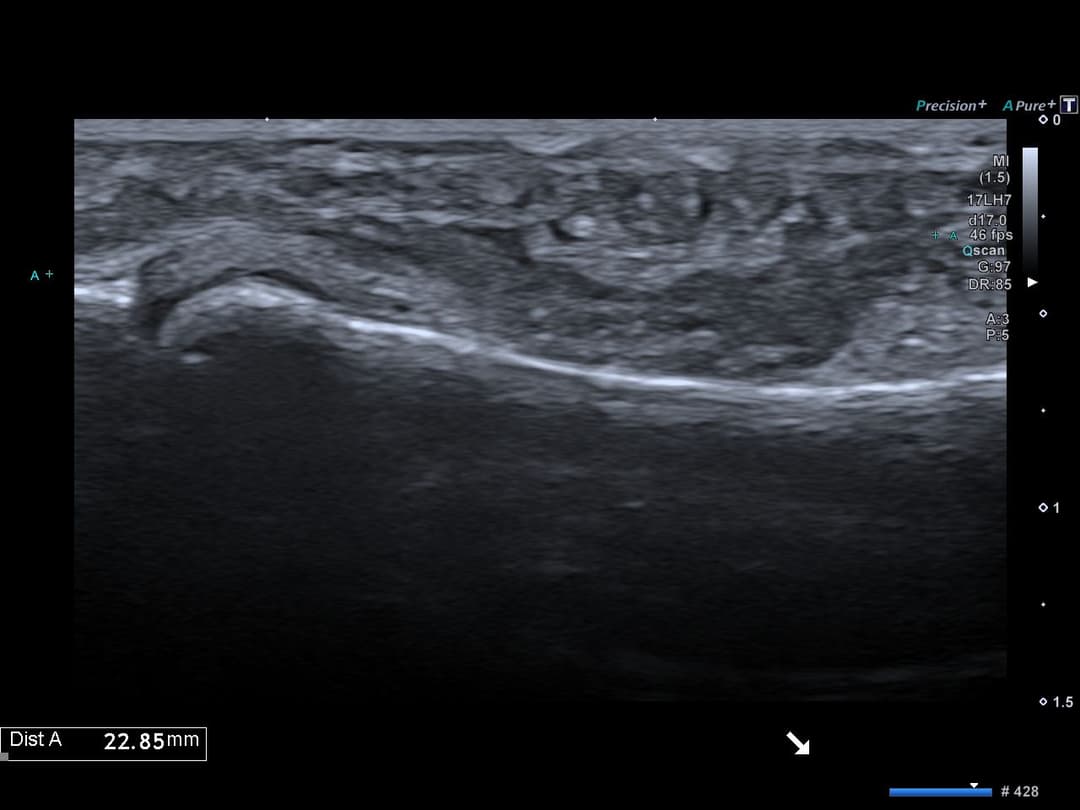

Échographie

Ecart interfragmentaire évaluée à 2.3 cm